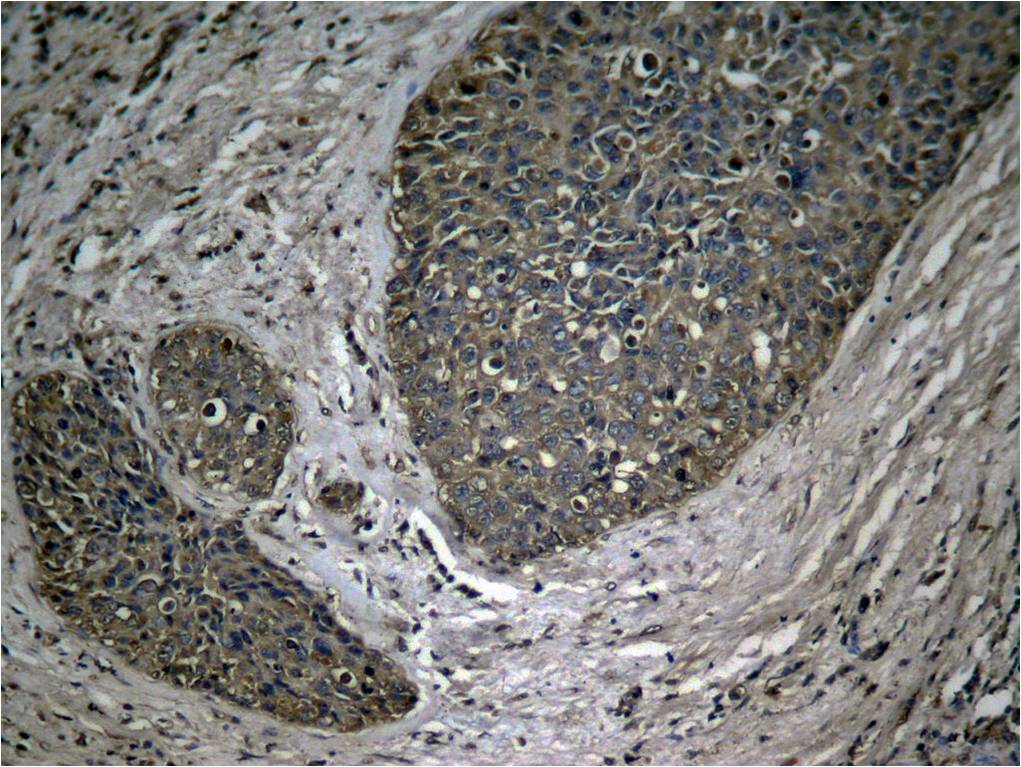

Product information "Anti-phospho-NFkB p65 (Ser536)"

| Application: | ICC, IF, IHC (paraffin), WB |